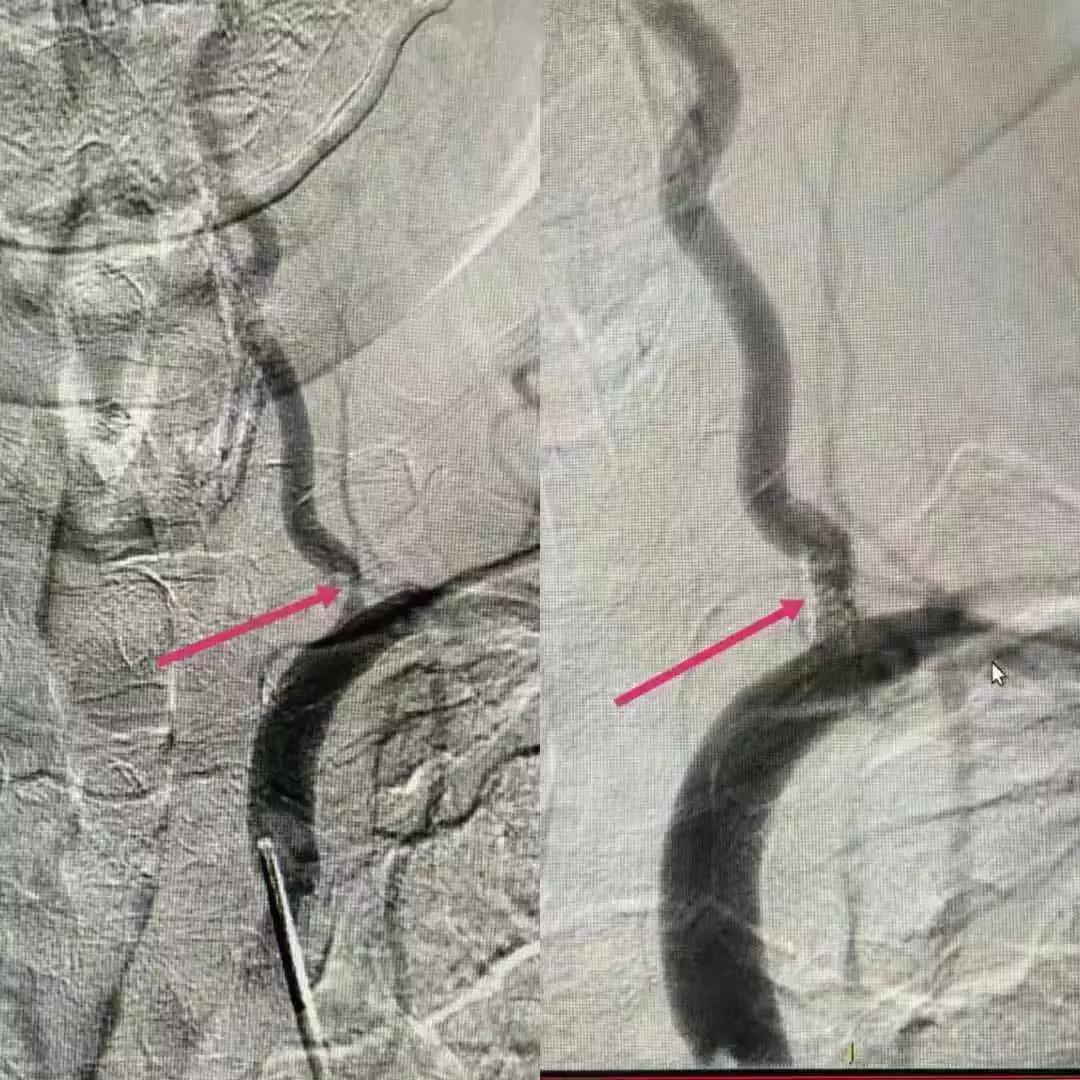

11月5日,我们针对患者手术险、急放药品的准备、术后患者的护理等进行讨论,护士长也积极参加,为术后患者的护理也做着准备,并且认真的标记出需关注的事项,以备对护理人员进行培训。11月6日中午,我们全部人员待命,手术持续一个半小时后于14:40顺利完成左侧颈内动脉、左侧椎动脉支架植入。支架植入术后,患者血管狭窄处管径基本恢复正常,血流通畅,脑灌注良好,患者头量症状消失,术后留院视察期间未再出现肢体麻木无力症状。